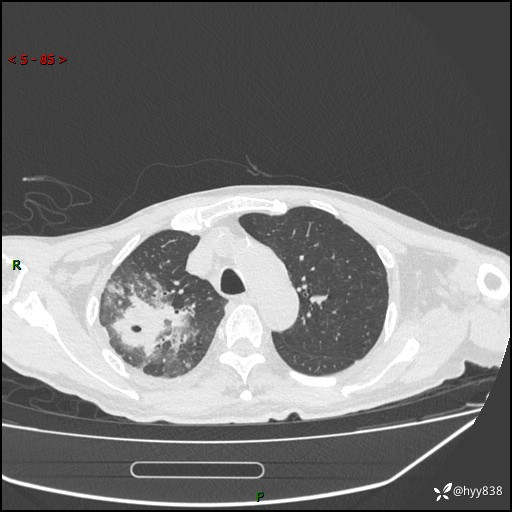

第一次胸部CT检查